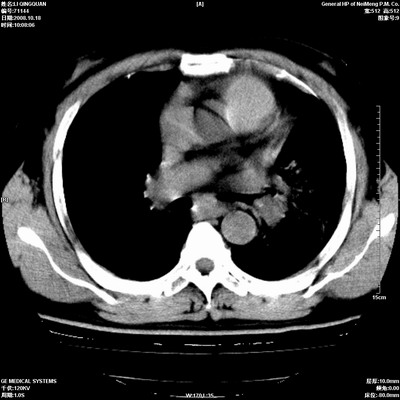

以下是引用duguo在2008-10-19 13:59:00的发言:[br]左肺上叶支气管狭窄,首先考虑中心型肺癌伴阻塞性肺炎\\肺不张.

以下是引用ybing在2008-10-19 12:58:00的发言:[br]左肺上叶阻塞性炎症-建议支气管镜进一步检查除外中央型肺癌

以下是引用随光逐影在2008-10-19 14:31:00的发言:[br]考虑左肺中央型肺癌并左肺上叶阻塞性肺炎,肺不张。